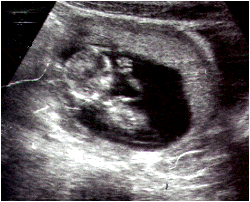

Ecografía de un feto de 18 semanas que muestra la actitud del feto con la mano sobre la cara.